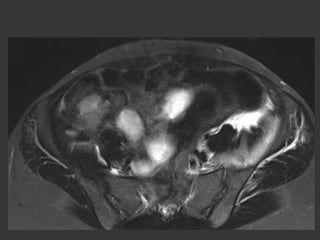

Mr C

36 year-old

Left Coxalgia for two

months

Inflammatory syndroma